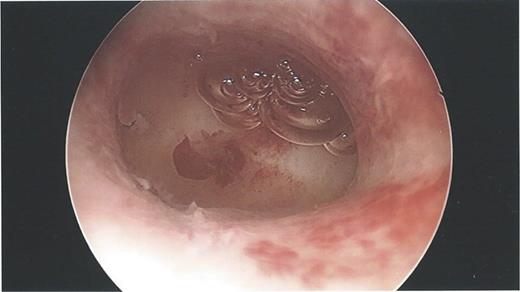

During the hysteroscopy 4 weeks later there was no evidence of an IUCD into the uterine cavity and no evidence of a perforation site in the uterus (Fig. 1). A laparoscopy followed, locating the coil threads deep in the Pouch of Douglas, with the IUCD perforating through the sigmoid colon into the lumen (Fig. 2). The IUCD was retrieved laparoscopically and the defect in the sigmoid colon was repaired by stapling the tear (Fig. 3).

Laparoscopy showing a sigmoid colon post-repair after removal of coil.